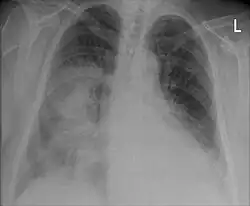

La neumonía se diagnostica con una combinación de la clínica que presenta el afectado, incluyendo tos, fiebre y dificultad respiratoria y confirmada por la consolidación pulmonar observable en una radiografía de tórax. La etiología se establece con cultivo bacteriológico del esputo y de la sangre (hemocultivo). A menudo una broncoscopia es indicada para ciertos pacientes hospitalizados.[9] El diagnóstico acertado puede ser difícil en pacientes con otras enfermedades. Ocasionalmente se emplea la tomografía y otros exámenes para diferenciar una neumonía de otras enfermedades, como el cáncer de pulmón.

Un examen importante para el diagnóstico acertado de una neumonía es la radiografía de tórax, que puede mostrar áreas de opacidad (vistas como zonas blanquecinas), que representan áreas de consolidación. La neumonía no siempre se puede apreciar en una radiografía de tórax, bien porque se trate de un estadio inicial de la enfermedad o porque se halle infectada una porción de los pulmones que no se observa en una radiografía. Una radiografía puede también ser difícil de interpretar en pacientes con fibrosis pulmonar e insuficiencia cardíaca congestiva.[11] En algunos casos se amerita realizar una tomografía computarizada.